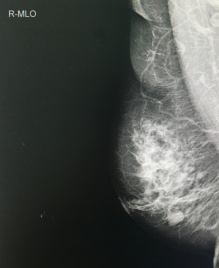

乳腺钼靶斜位片

如前述,年轻女性腺体致密,钼靶检查会更痛苦,也更容易遗漏病灶,因此,作为筛查手段,年轻女性、腺体致密或有乳腺增生史者优先选择超声检查,而年龄偏大、腺体退化、乳腺脂肪成分偏多者适宜选择钼靶检查。另外,超声对辨别肿块有优势,还可以区分实性肿块和囊性肿块,但对细小钙化敏感度较差,钼靶检查对于小钙化灶敏感度极高,很多时候恶性钙化灶是许多乳腺癌唯一或者特征性的征象,因此,两项检查很多时候并不能相互取代,而是相互补充,两项检查相互结合为检查乳腺疾病的“黄金搭档”。